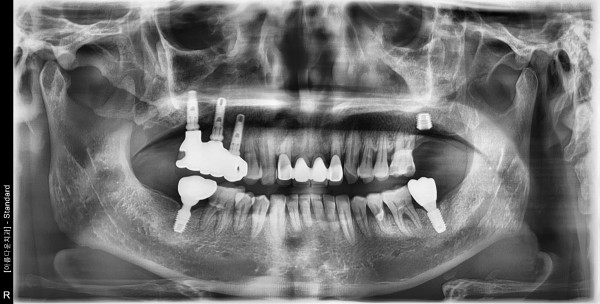

60대 남성 임플란트 식립

2bbed4f5a66a6508b7cf5ac7d6acce9e_1760322